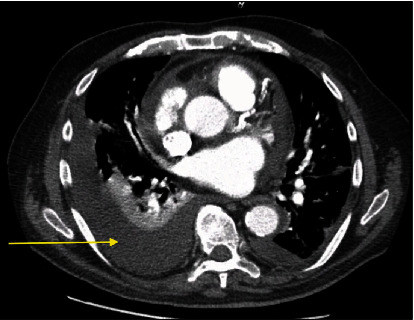

Uremic pericardial effusion and pericarditis in end-stage kidney disease patients remain one of the causes responsible for high rates of morbidity and occasional mortality. While clinical presentation could be variable, clinicians should have a high index of suspicion for uremic pericarditis especially in patients who miss their dialysis sessions. We present a 77-year-old man with end-stage renal disease on dialysis diagnosed with pericarditis and large pericardial effusion complicated by cardiac tamponade and shock. He underwent urgent pericardiocentesis with clinical improvement. The course of the disease can be complicated by shock with multiorgan failure, particularly the liver. The presentation is relatively acute requiring a high level of suspicion, urgent diagnosis, and management to reduce mortality. As the geriatric population increases with associated comorbid conditions, it would be expected that patients undergoing dialysis would increase. Given the uncommon nature of the disease and how these patients have been managed by multiple specialties and care providers, it is important to consider dialysis-related complications in all patients with end-stage renal disease presenting with dyspnea.